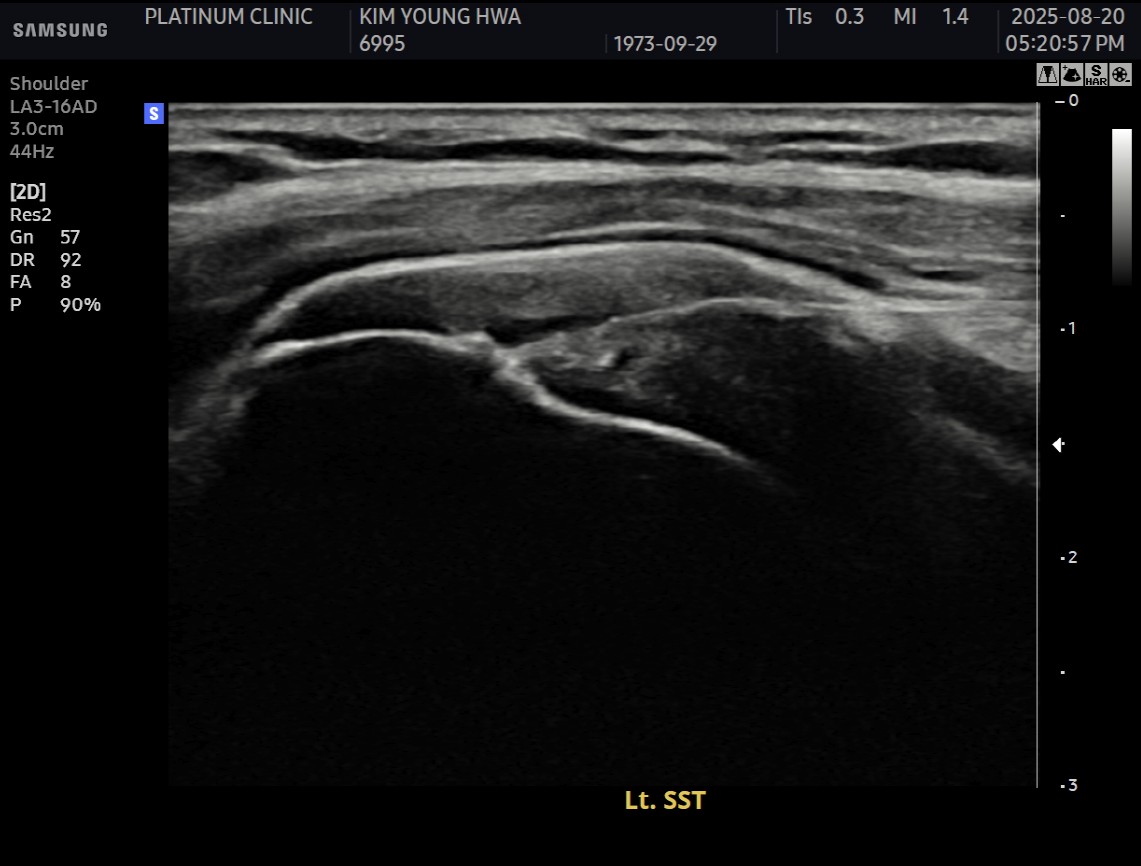

MRI와 초음파 검사 결과:

진단 결과:

- ✓관절면측 부분파열: 약 50%

- ✓점액낭면측 부분파열: 약 35%, 인대 얇아짐 동반

- ✓25년간 반복 사용으로 인한 퇴행성 변화 동반

양쪽 모두 손상된 복합 파열이었습니다.

시술 과정

시술 시간: 약 40분

6개월 후:

- ✓관절면측: 봉합 부위 안정적 유지

- ✓점액낭면측: 인대 두께 4.8mm → 6.5mm (1.7mm 증가)

현재: 정상적인 정육점 업무 복귀. 30kg 고기도 문제없이 들어올림.